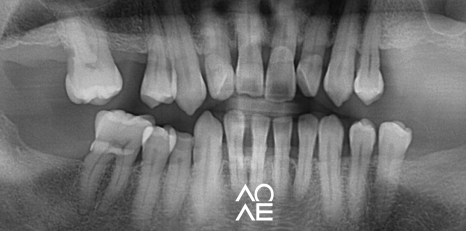

방사선 검사 등을 꼼꼼하게 진행해보니

교정이 아닌 크라운으로 치료가 가능한

구강 상태를 가지고 계셨기에 크라운 치료를

결정하고 진행하게 되었습니다.

개별 보철을 통해서

관리를 잘 하실 수 있게

보철물을 제작해 드렸습니다

그래서 보철물을 개별로 하나 하나씩 제작해서

치료를 마무리 해드렸습니다.

| 치료 전(23. 12. 03) | 치료 후(24.06. 20) |